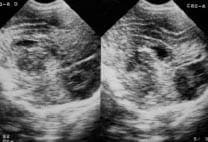

Se le realizó ecografía cerebral transfontanelar en la primera y segunda semana postnatal que evidenciaron hemorragia de la matriz germinal GI; posteriormente, durante su estancia presentó aumento del perímetro cefálico, fontanela anterior tensa, una nueva ecografía de SNC (Foto 8) ya demuestra hidrocefalia con dilatación del tercer ventrículo y los ventrículos laterales, el cuarto ventrículo es normal.

Foto 8. Ecografía cerebral trasnsfontanelar.